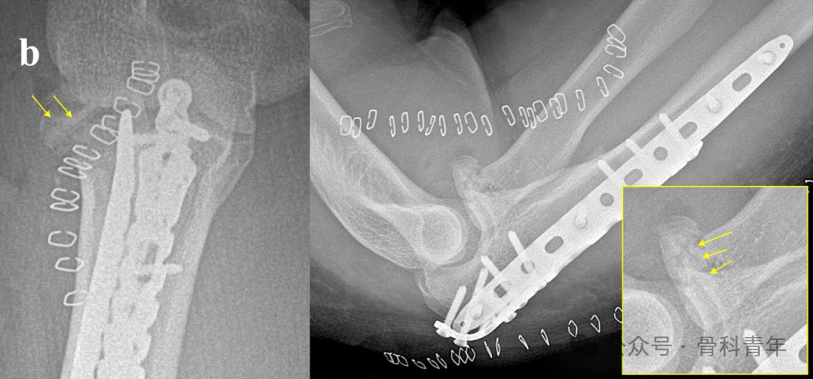

步骤三:将粉碎骨块复位,采用可吸收螺钉工具(钻头、丝攻、螺丝刀),置入可吸收螺钉。为了获得最好的把持力,可将螺钉置入软骨平面下方2-4mm。

步骤五:可吸收克氏针的处理上,最重要在于将尾部剪断后,采用磨头将克氏针磨平,并使其低于关节软骨面,避免局部刺激。

病例2:内侧副韧带止点撕脱骨折合并II型桡骨头骨折,2枚可吸收螺钉固定。